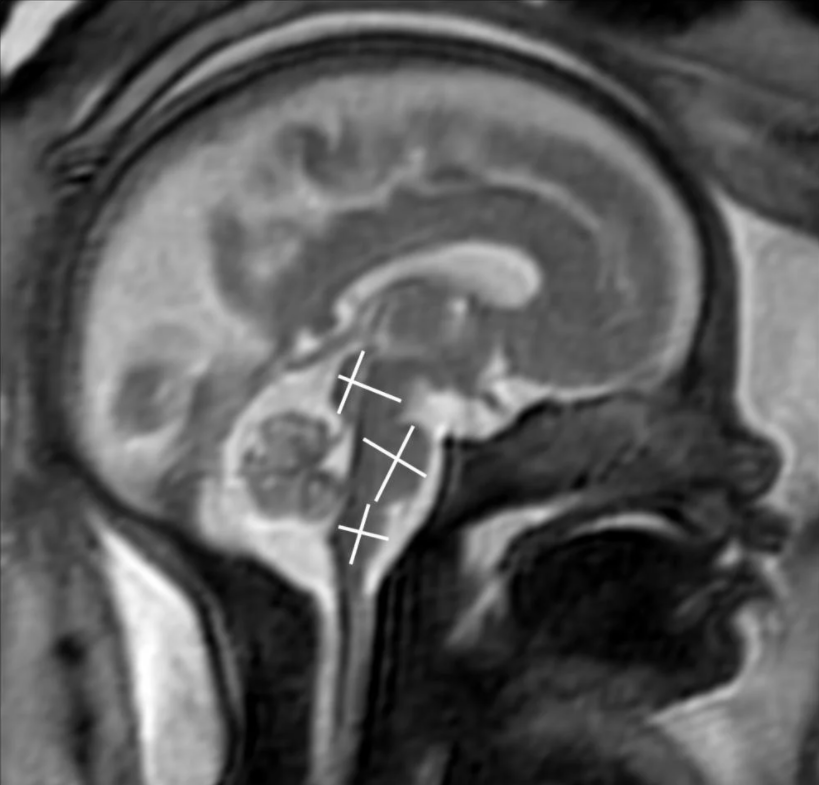

This photo gallery shows the variety of radiological presentations of COVID-19 (SARS-CoV-2) in medical imaging, including computed tomography (CT), radiograph X-rays, ultrasound, echocardiograms and magnetic resonance imaging (MRI). The radiology images show examples of typical COVID pneumonia in the lungs and the numerous complications the virus causes in the body in multiple organs, including the brain, kidneys, heart, abdomen and vascular system.

The images were collected from physicians, study authors, universities and hospitals, the National Institutes of Health (NIH), the Radiological Society of North America (RSNA), the American College of Radiology (ACR), Centers for Disease Control and Prevention (CDC) and radiology technology vendors.